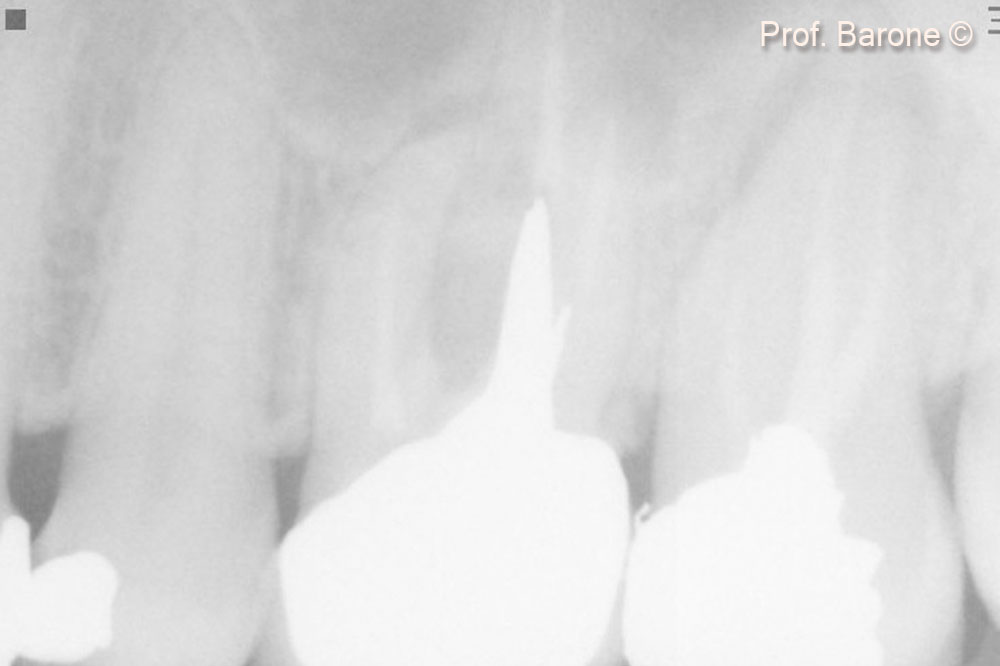

Periapical Radiograph